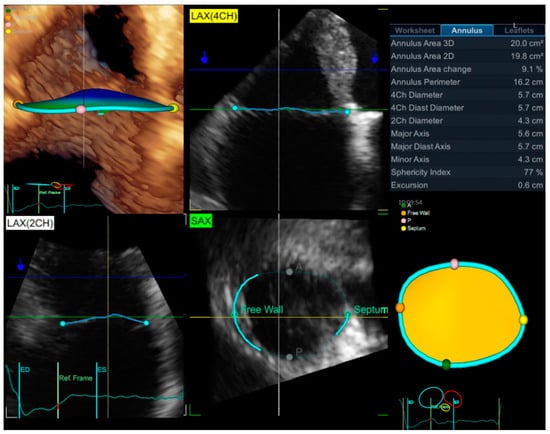

3.1. Echocardiography